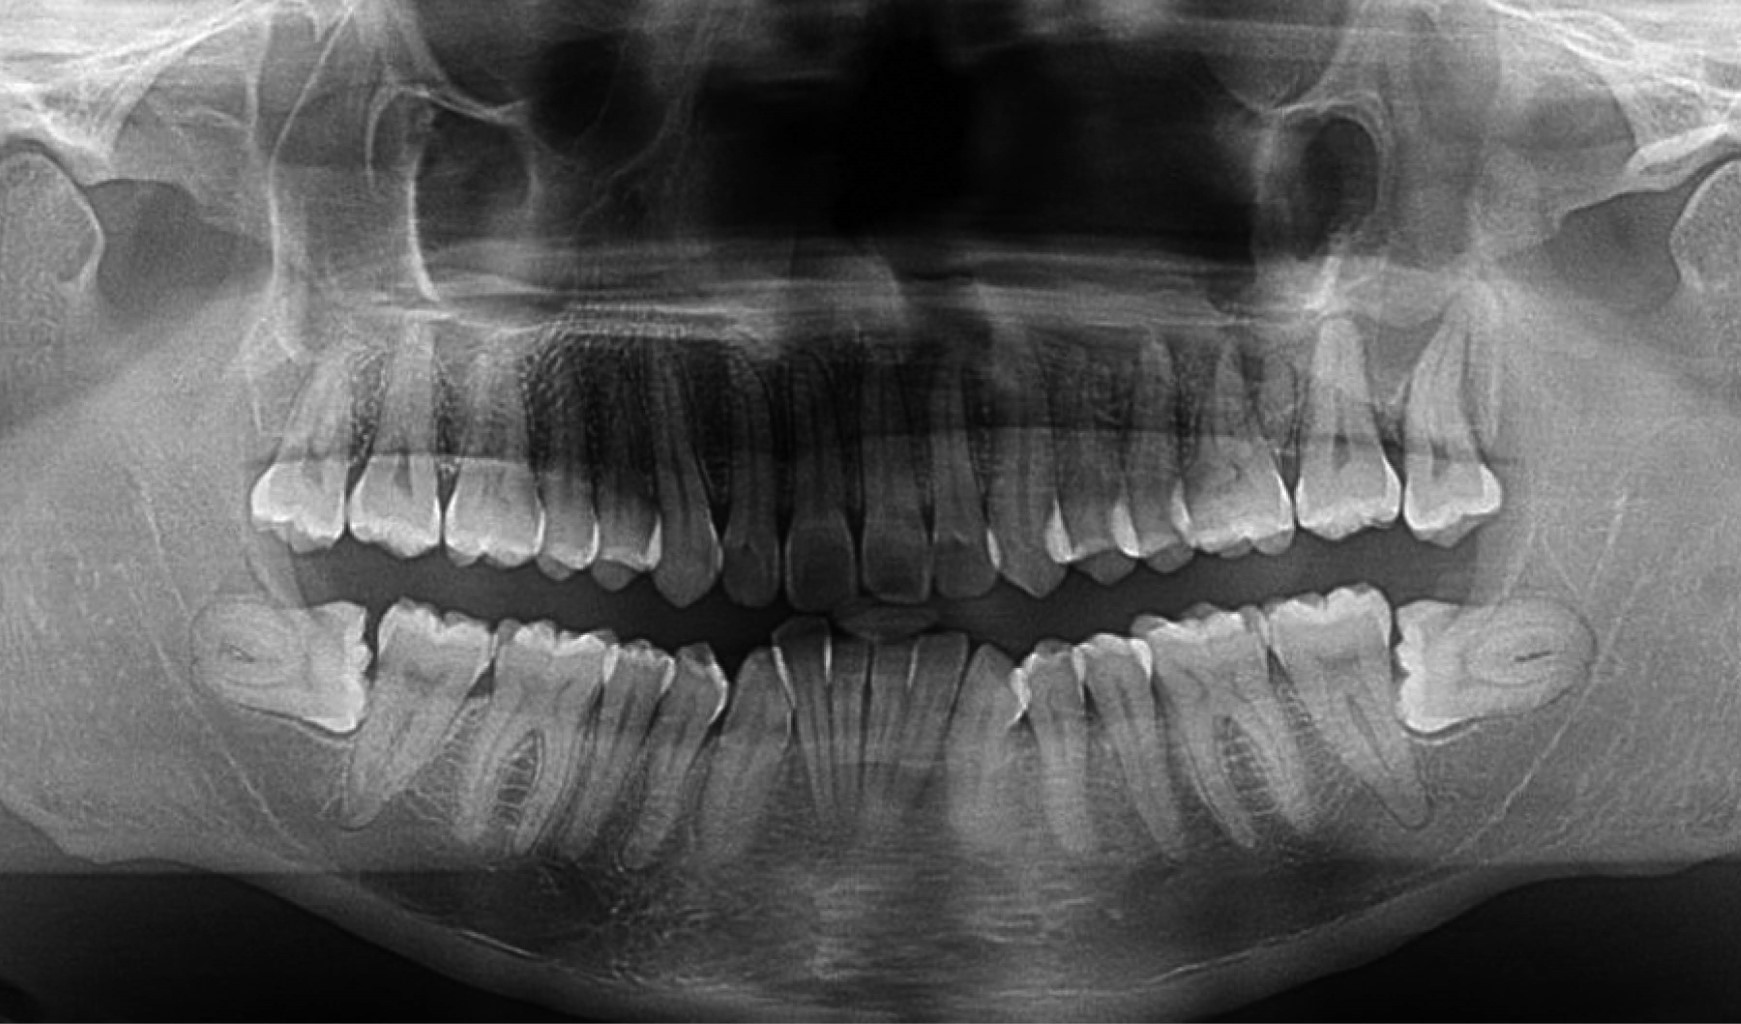

Durante el seguimiento, en 2021 el paciente refirió aumento de volumen en la región malar izquierda, asociado a molestias en el tercer molar superior derecho (Figura 1). En 2023, se documentaron signos clínicos compatibles con osteorradionecrosis maxilar, con evidencia de necrosis ósea. Se indicó la realización de una biopsia, en la cual se identificó infección por Actinomyces (Figura 2). Posteriormente se observó progresión de la lesión en el sitio de la biopsia, con evidencia de comunicación hacia el piso de la cavidad nasal, movilidad dentaria y dolor persistente. El abordaje terapéutico incluyó manejo antibiótico y administración del esquema PENTOCLO (pentoxifilina + tocoferol).

En 2025 fue referido al servicio de estomatología del INCan debido a movilidad grado 3 de piezas dentales del maxilar por pérdida de soporte óseo. Se discutió el caso con el servicio de radioterapia para autorizar extracciones dentales, y en conjunto con el servicio de cirugía maxilofacial se llevaron a cabo múltiples extracciones dentales y desbridamiento del secuestro óseo bajo anestesia local, sin complicaciones (Figura 3). Se indicó continuar con el tratamiento con PENTOCLO y el sujeto fue integrado a manejo paliativo integral, debido a la progresión sistémica de la enfermedad oncológica, con metástasis pulmonares y en otros sitios (Figura 4).

Figura 3

Figura 4